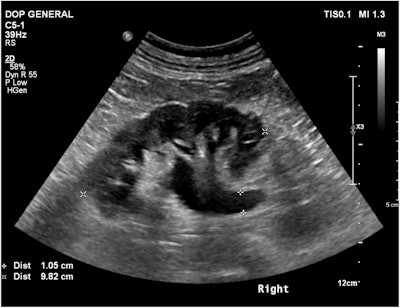

Ultrasound image of the right kidney demonstrating hydronephrosis from the previous analysis. GPT-4V identified the modality but misidentified the anatomical region as “pelvis” and the pathology as “cholelithiasis”.Brin et al; European Radiology

In comparison, GPT-5 also demonstrated 100% accuracy in identifying the modality used. Its performance was significantly better than that of GPT-4V with regard to anatomical localization: 97.8% overall; 100% for CT, 98.1% for x-ray, and 94.6% for ultrasound. Improvements in pathology identification were less pronounced, at 40% overall.

The authors added that the improvement in pathology accuracy was largely seen in ultrasound, with the rate rising from 9.1% to 33.8%. Pathology showed a more modest improvement for x-ray (67.9% for GPT-5 vs. GPT-4V’s 66.7%.) However, the accuracy rate for pathology-level identification for CT was lower for GPT-5 than for GPT-4V: It had decreased from 36.4% to 30.1%.

Even with the improvements in anatomical and pathology identification, the authors determined that GPT-5 exhibited the same shortcomings with errors as GPT-4V. In fact, the rate of hallucinations had worsened: 60% of the total number of exams with the updated software now had at least one hallucinated finding, while that percentage had been 46.8% with the previous version. The percentages by modality were all higher -- 73.8% for CT (GPT-4V: 51.5%), 26.4% for x-ray (GPT-4V: 19.6%), and 64.9% for ultrasound (GPT-4V: 60.6%).